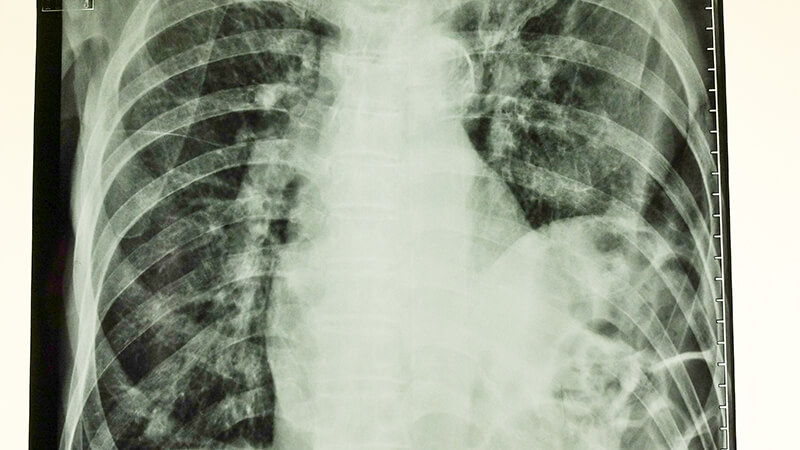

Η διάγνωση του τραυματισμού του διαφράγματος μπορεί να διαλάθει, καθώς, εκτός από τις περιπτώσεις εκείνες στις οποίες συνοδεύεται από οξεία πρόπτωση των κοιλιακών σπλάγχνων στο θώρακα, όπως φαίνεται στην ακτινογραφία της εικόνας, δε συνοδεύεται από ειδικά συμπτώματα ή σημεία, ενώ και η απεικόνιση του, παρά τη σύγχρονη απεικονιστική τεχνολογία, μπορεί να μην αποκαλύψει μικρής έκτασης κακώσεις.

Στην απλά ακτινογραφία θώρακος, το ημιδιάφραγμα (συνήθως το αριστερό, διότι το δεξιό προστατεύεται σε κάποιο βαθμό από το ήπαρ) βρίσκεται σε θέση υψηλότερη της φυσιολογικής, ενώ εντός του ημιθωρακίου μπορεί να παρατηρούνται εντερικές έλικες. Η κατάσταση αυτή βέβαια αναπαριστά μία μεγάλης έκτασης ρήξη του ημιδιαφράγματος. Σε μικρότερης έκτασης τραυματισμούς, η διάγνωση της ρήξης του διαφράγματος με τη βοήθεια της ακτινογραφίας θώρακα, είναι πολύ δύσκολη